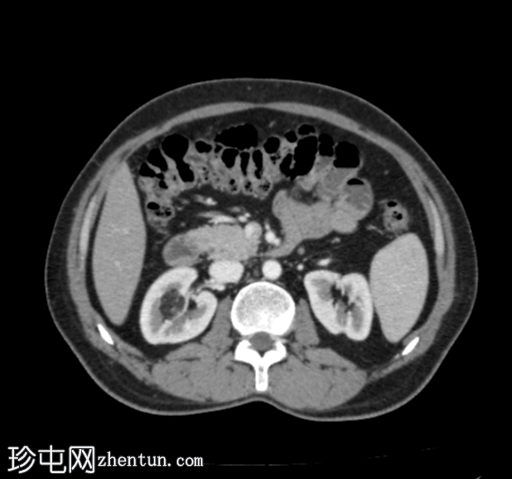

轴位增强扫描(门静脉期)

CT扫描显示右肾上半部可见一部分边界清晰的肿块,其密度成分包含软组织和脂肪。

其余腹腔脏器未见明显异常。

可见累及L4椎体的血管瘤。

目前的CT

影像

学表现为右侧肾血管平滑肌脂肪瘤,无内部出血。